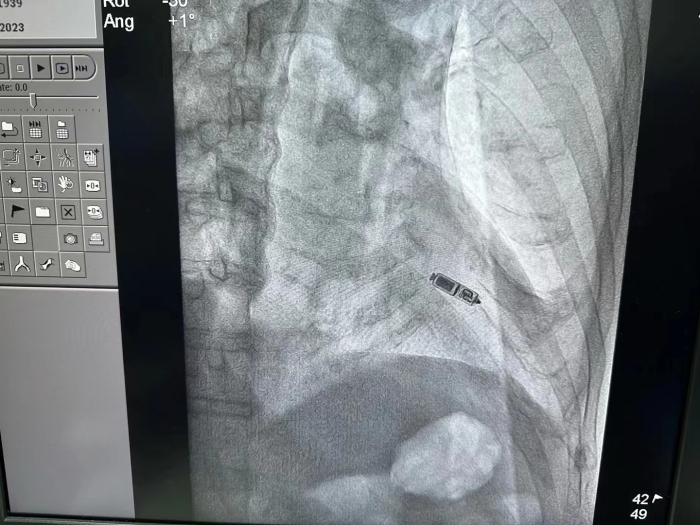

11月7日,浙江省人民医院毕节医院(以下简称“毕节医院”)心血管内科成功为84岁患者开展Micra(无导线心脏起搏器)植入术,第二天便出院,在全市尚属首例,标志着毕节医院对心律失常的诊治水平再上一个新台阶。

心血管内科经过缜密的诊疗分析,并制定了可行的手术方案。在与患者及家属进行了充分的沟通后,11月7日,心血管内科手术团队在云南省阜外心血管病医院心律失常一病区主任、主任医师郭涛的指导下,成功为患者完成Micra(无导线心脏起搏器)植入术。

术后,起搏器程控显示起搏器工作状态良好,起搏与感知功能正常,患者第二天出院。

Micra无导线心脏起搏器被誉为“全球体积最小的心脏起搏器”。体积仅有胶囊大小,无需植入心内膜导线,也无需在胸前皮下制作囊袋放置脉冲发生器(起搏器),减少了创伤与感染风险。

而且Micra(无导线心脏起搏器)直接植入在心腔内,无伤疤、无切口,患者在植入后几乎感觉不到起搏器的存在,大大改善了患者的生存质量。